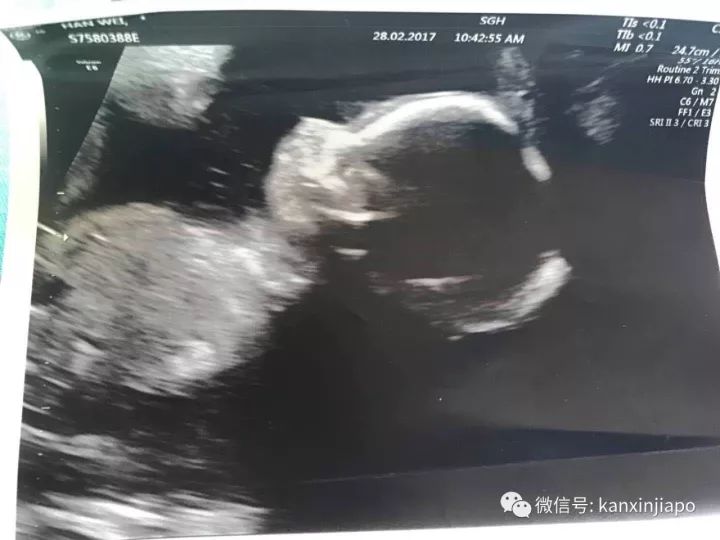

(B超图)

之后,张太太的肚疼并没有缓解,她于3月3日再次就医。这次医生说根据之前的尿检,她的白带和尿都很干净,没有感染细菌。另外她还做了B超,可以看到宝宝在肚子里活动,很健康。